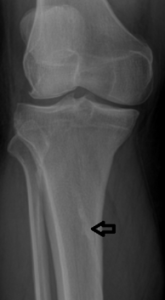

3. Prominent Soleal Line

Figure 4 demonstrates prominent ossification that obliquely traverses the proximal tibia at the origin of the soleus muscle. Figure 5 demonstrates a thick osseous protrusion along the posterior tibia. This normal variant can be mistaken for an aggressive periosteal reaction or pathologic heterotopic ossification. But the anatomic orientation of the ossification along the soleal insertion and no involvment of the underlying bone should allow the clinician to easily identify this variant. This normal viariant has also been termed tibial pseudoperiostitis or tibial tug lesion.